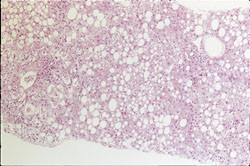

Blodprøver viste moderat forhøyede verdier for alaninaminotransferase (ALAT) og aspartataminotransferase (ASAT) og markert forhøyet serum-ferritinnivå med samtidig normal transferrinmetning og negativ gentest for hemokromatose (tab 1). Ultralydundersøkelse og computertomografi av lever viste forandringer forenlig med steatose. Leverbiopsi viste betydelig steatose (fig 1) og jernavleiring (fig 2) (tab 2). Det var ikke holdepunkt for viral eller autoimmun leversykdom og verdier for serum-pipider var normale (tab 1).